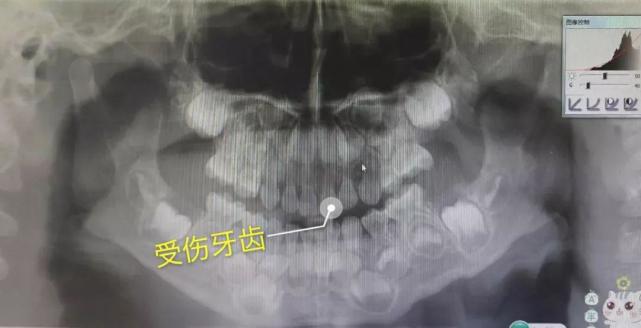

医生说,拍个片子看看。片子看过之后,医生说,牙神经受损了,里面发炎了,已经形成瘘管,必须要做根管治疗,如果现在不做以后会影响恒牙的萌出。

图片

△ 正中间那颗受伤的牙齿已经出现了牙根吸收的状况,白色的一粒一粒的是宝贝的恒牙牙胚。

医生指着娃的牙片跟我说,宝宝(小宝宝出生时就有20个乳牙和28个恒牙牙胚在颌骨里生长了)乳牙牙根和恒牙牙胚之间的距离很小,乳牙受到撞击的时候,可能会影响到里面恒牙的成长。

△ 第二次拍的牙片,可以看到这颗受伤的门牙的牙根明显比旁边那颗短很多。

一一是撞击导致牙髓发炎,因为我们没有即时发现,形成瘘管在牙龈上鼓起了包。从片子上看,恒牙的胚囊已经受到影响,牙根出现了吸收的状况。在取出牙根后发现,牙根已经完全没有弹性了(正常的牙根是有弹性的),说明这颗牙受伤已经有段时间了。